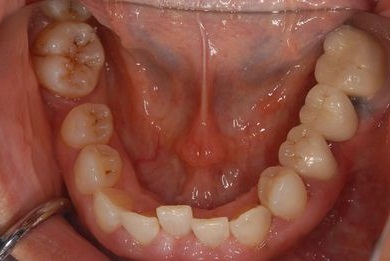

抜歯即日スピードインプラント治療

| 性別/年齢 | 女性 / 52歳 | ||||||||||||||||||||||||||||||||

| 主訴 | 歯周病で歯の位置がずれてしまった。 | ||||||||||||||||||||||||||||||||

| 治療内容 | インプラント2本(抜歯即日スピードインプラント)、メタルボンドセラミッククラウン4本 | ||||||||||||||||||||||||||||||||

| 総治療費 | 1,269,450円 | ||||||||||||||||||||||||||||||||

| 治療期間 | 10ヶ月 |